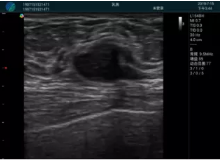

腺體內部清晰顯示一低回聲塊影,形態(tài)不規(guī)則,邊界模糊,邊緣呈毛刺狀,內部見砂礫樣鈣化

M20引導下穿刺活檢術

M20引導下平面內穿刺取出的腫塊組織